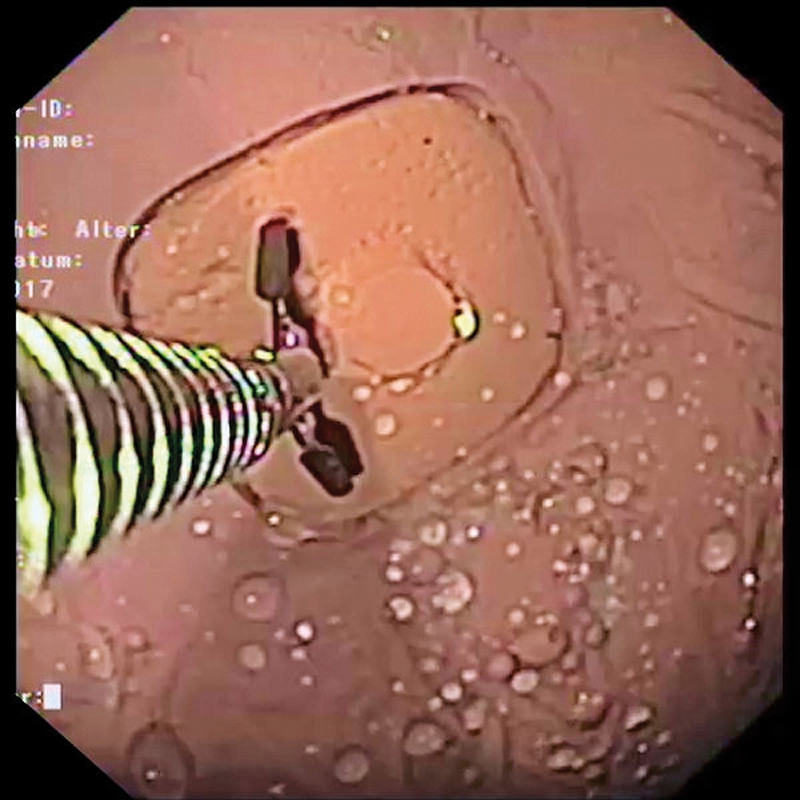

Simulator Gastro združuje možnosti realističnega anatomskega modela in usposabljanja za intervencijsko endoskopijo. Veliko število različnih vložkov omogoča zdravljenje polipov, kot so vbrizgavanje, dvigovanje, rezanje in odstranjevanje, simulacija zaustavitve krvavitve, stentiranje in drugo. Simulator in vložki so izdelani iz popolnoma umetnega materiala.

- Odstranjevanje tkiva s hladno zanko, npr. polipektomija

- Odvzem biopsije tkiva s kleščami

- Zdravljenje krvavitev / zaustavljanje krvavitev z injekcijami, sponkami in ligiranjem traku